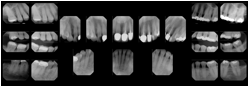

2. A patient requests cosmetic surgery to enhance their facial appearance. The case requires consultation between an orthodontist in New York and an oral surgeon in California. The cephalometric series of 2D projections constructed from the volumetric CT data that is used for the discussion is arranged by a Structured Display for transfer between the two practitioners.

Cephalometric Series Structured Display

Figure OO-2. Cephalometric Series Structured Display